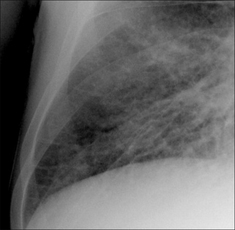

Figure 28.6 Chronic dyspnoea. Apply Golden Rule 3—you only look for what you know. Fine interstitial lines and nodules in the right lower zone. The same appearance was evident in the left lower zone. CXR conclusion—interstitial fibrosis. Subsequently confirmed.